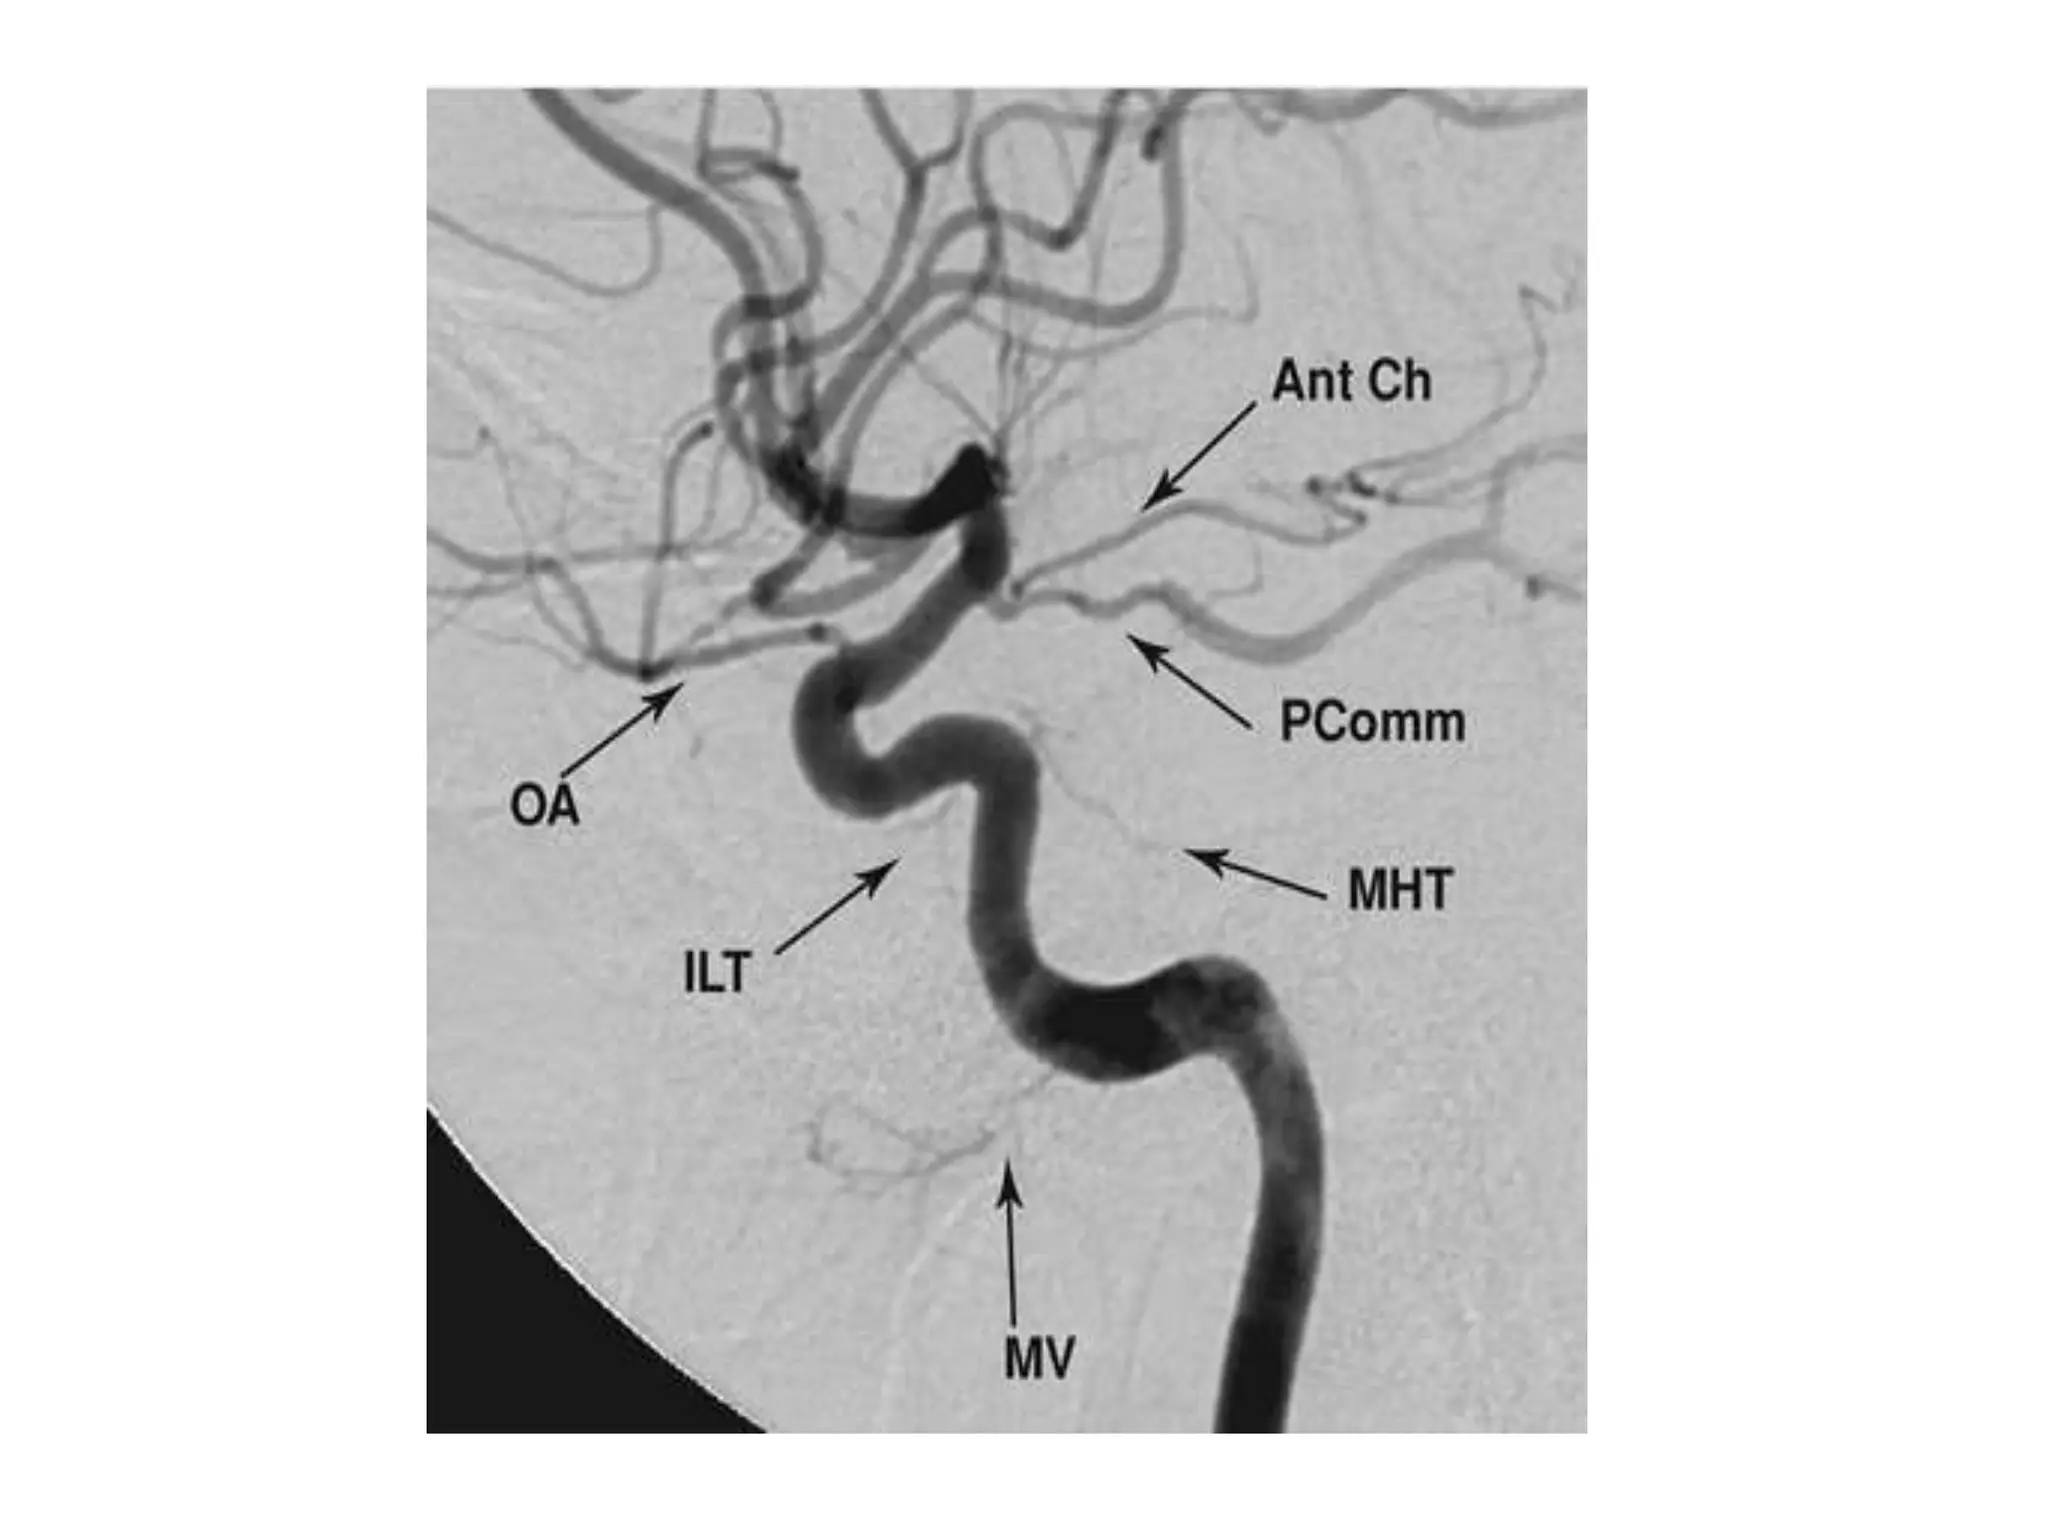

2-Parasellar Zone :

-In the parasellar region , the ILT and

meningohypophyseal trunk (MHT) arise

from the ICA

-They give branches which anastomose with

branches of IMA and APA

-The posterior branches of the ILT are

closely related to the dural branches of the

MHT

-The ILT is the key to understanding the real

and potential anastomoses that exist in the

parasellar region :